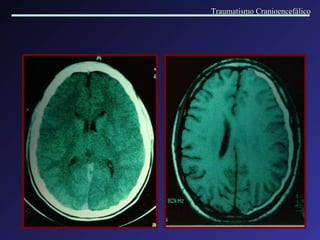

Hematomas subdurais bilaterais, com diferentes idades (crônico à direita e agudo à esquerda), associados a atrofia . Hematomas subdurais bilaterais agudos. Traumatismo Cranioencefálico

Hematoma Subdural Crônico Aparecem 20 dias após o trauma. Mecanismos: transudação de proteínas; hemorragias recorrentes. Variabilidade de manifestações clínicas. Traumatismo Cranioencefálico

Traumatismo Cranioencefálico